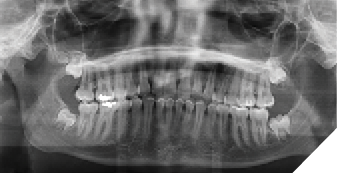

A 15-year-old female was referred for evaluation of impacted third molars. She was asymptomatic with a noncontributory medical history. Clinically, the impacted teeth exhibited completes emergence with no permucosal exposure. Panoramic radiography confirmed impaction of teeth #18, 28, 38 and 48, with suspected early development of a right maxillary supernumerary fourth molar. The maxillary third molars were positioned high in the maxilla, and surgery was deferred to allow further descent of these teeth (Fig. 1).

Fig. 1